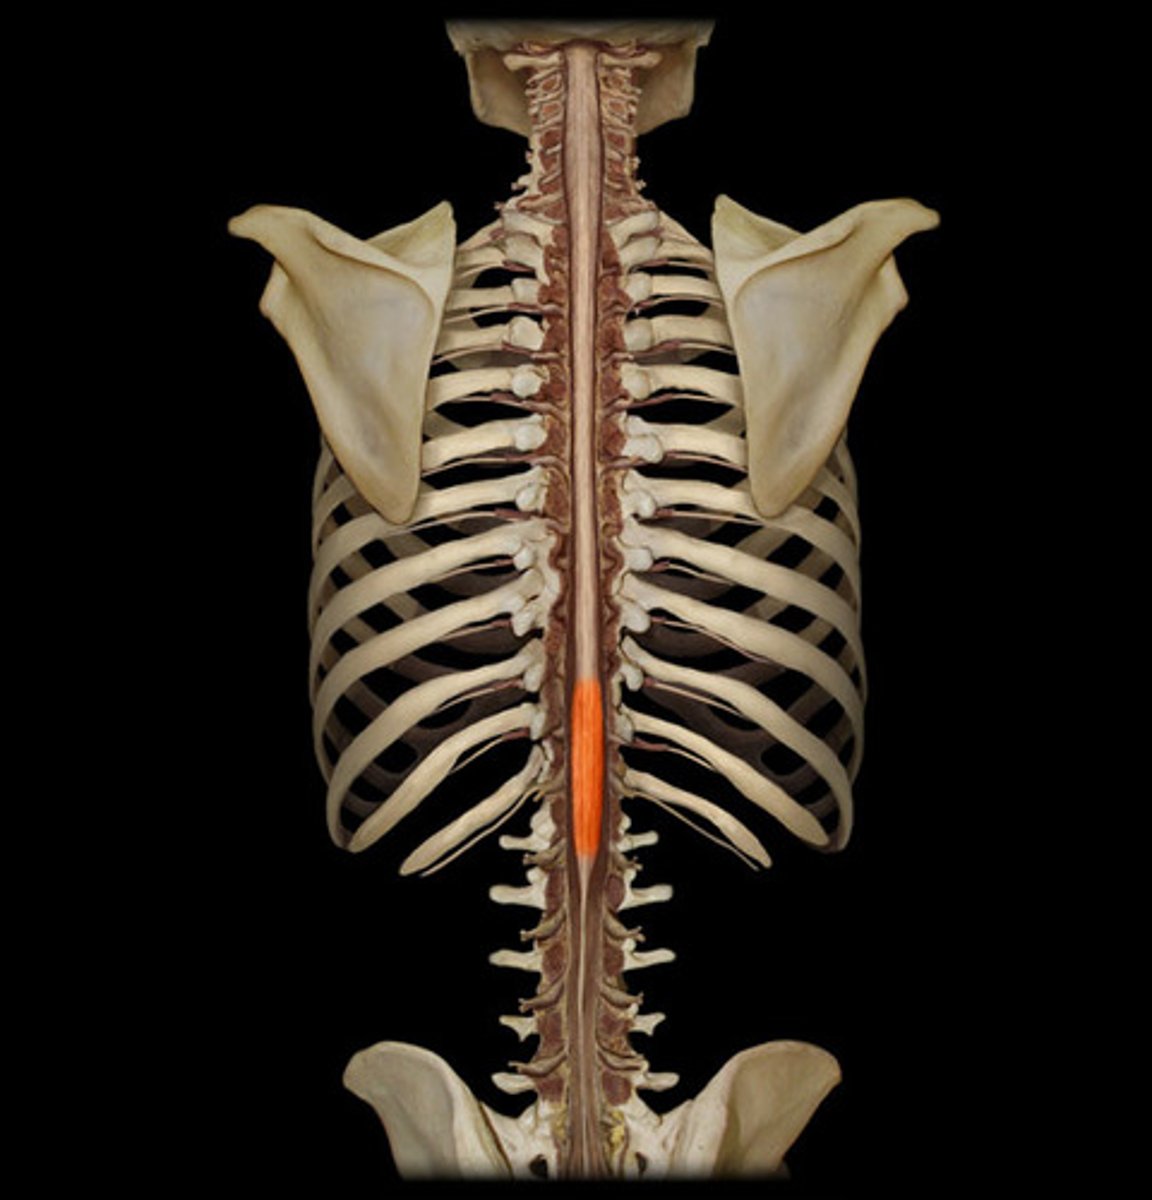

cervical enlargement

lumbar enlargement

conus medullaris